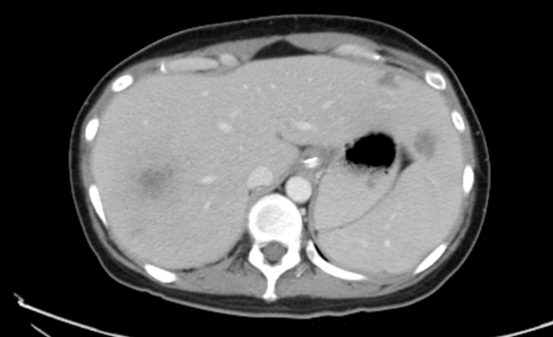

Plasma and peripheral blood mononuclear cell EBV were dropped dramatically from 235,767 IU/ml and 218,411 IU/ug on day -1 to 1,177 IU/ml and 1,747 IU/ug, respectively, on day +6 and then declined gradually until they were undetected on day +34 (figure 1). Prior “intrahepatic PTLD nodules” biopsy performed on +20 days showed total necrotic tissues except one cell stained positive for EBV, indicating the prior intrahepatic PTLD became necrotic and resolved in the subsequent months (Figure 2). At the time of report in July 2022, the patient got well and is living with persisted PTLD-free conditions in liver and undetected EBV PCR in plasma and PBMN cell as well.

Figure 2B Intrahepatic infiltrative lesions 3 weeks after second haplo-transplant.

2021/02/15